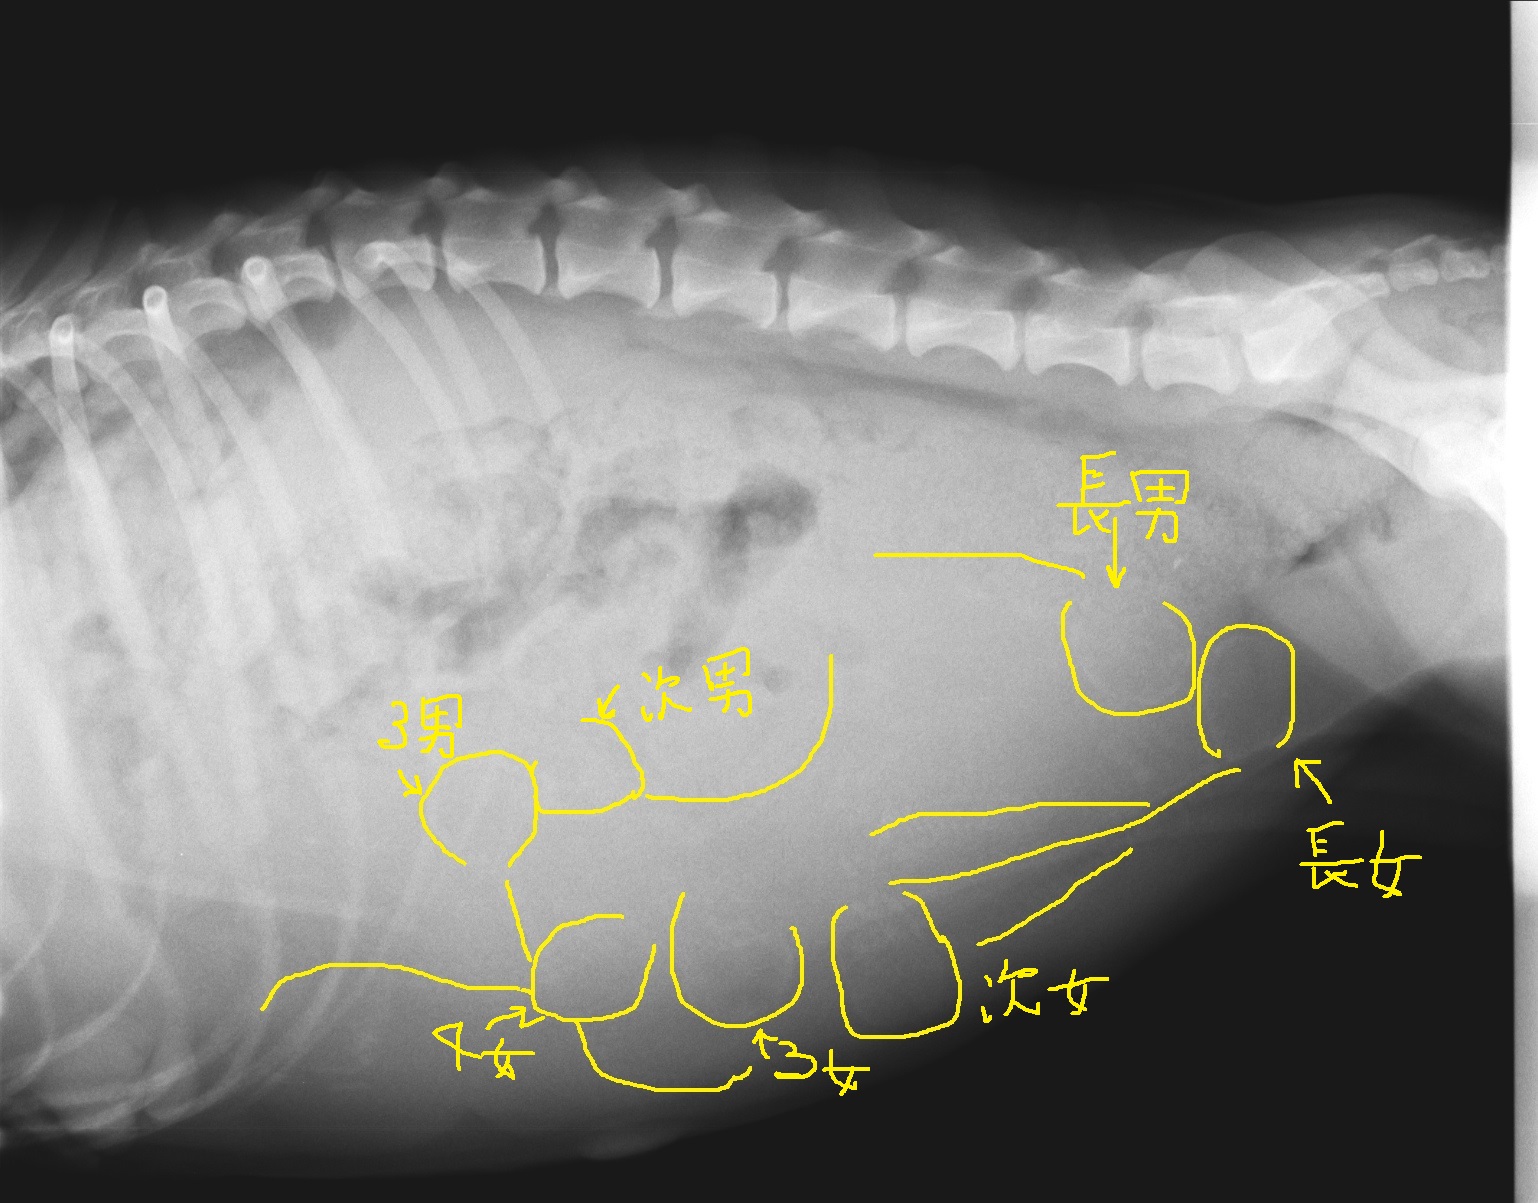

2017年9月7日生 ♂3 ♀4

2017.09.07生 ♂3 ♀4

2017年9月7日生 予定日は、9月9日

1 10:55 長女 品川区 Kok様ご愛犬リズちゃん

2 11:40 長男 港区 Mat様ご愛犬

3 13:02 次女 足立区 Hat様ご愛犬ベルちゃん

4 13:50 次男 八千代市 Min様ご愛犬アルバートくん

5 14:54 3女 横浜市緑区 Hay様ご愛犬ソフィーちゃん

6 16:27 3男 さいたま市 Kas様ご愛犬ルーカスくん

7 17:53 4女 鎌倉市 Mor様ご愛犬エラちゃん

R組のKate・JJの子犬達 1歳のお誕生日おめでとう

ございます。

予定日より2日早く午前中に産まれてあたふたしましたが、

全員健康で、無事に産まれて来てくれました。